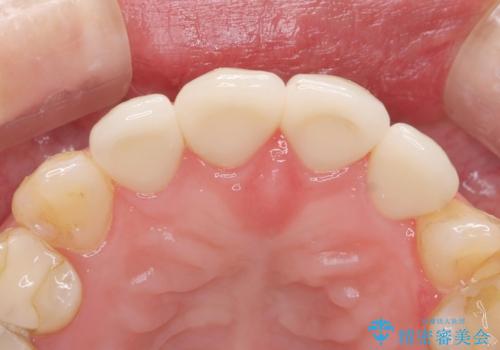

- ジルコニアクラウンスタンダード・仮歯 12.1万円×4費用は治療当時の料金となります

綺麗な被せ物が入りました。

現在犬歯も被せ物処置を行うか検討中です。